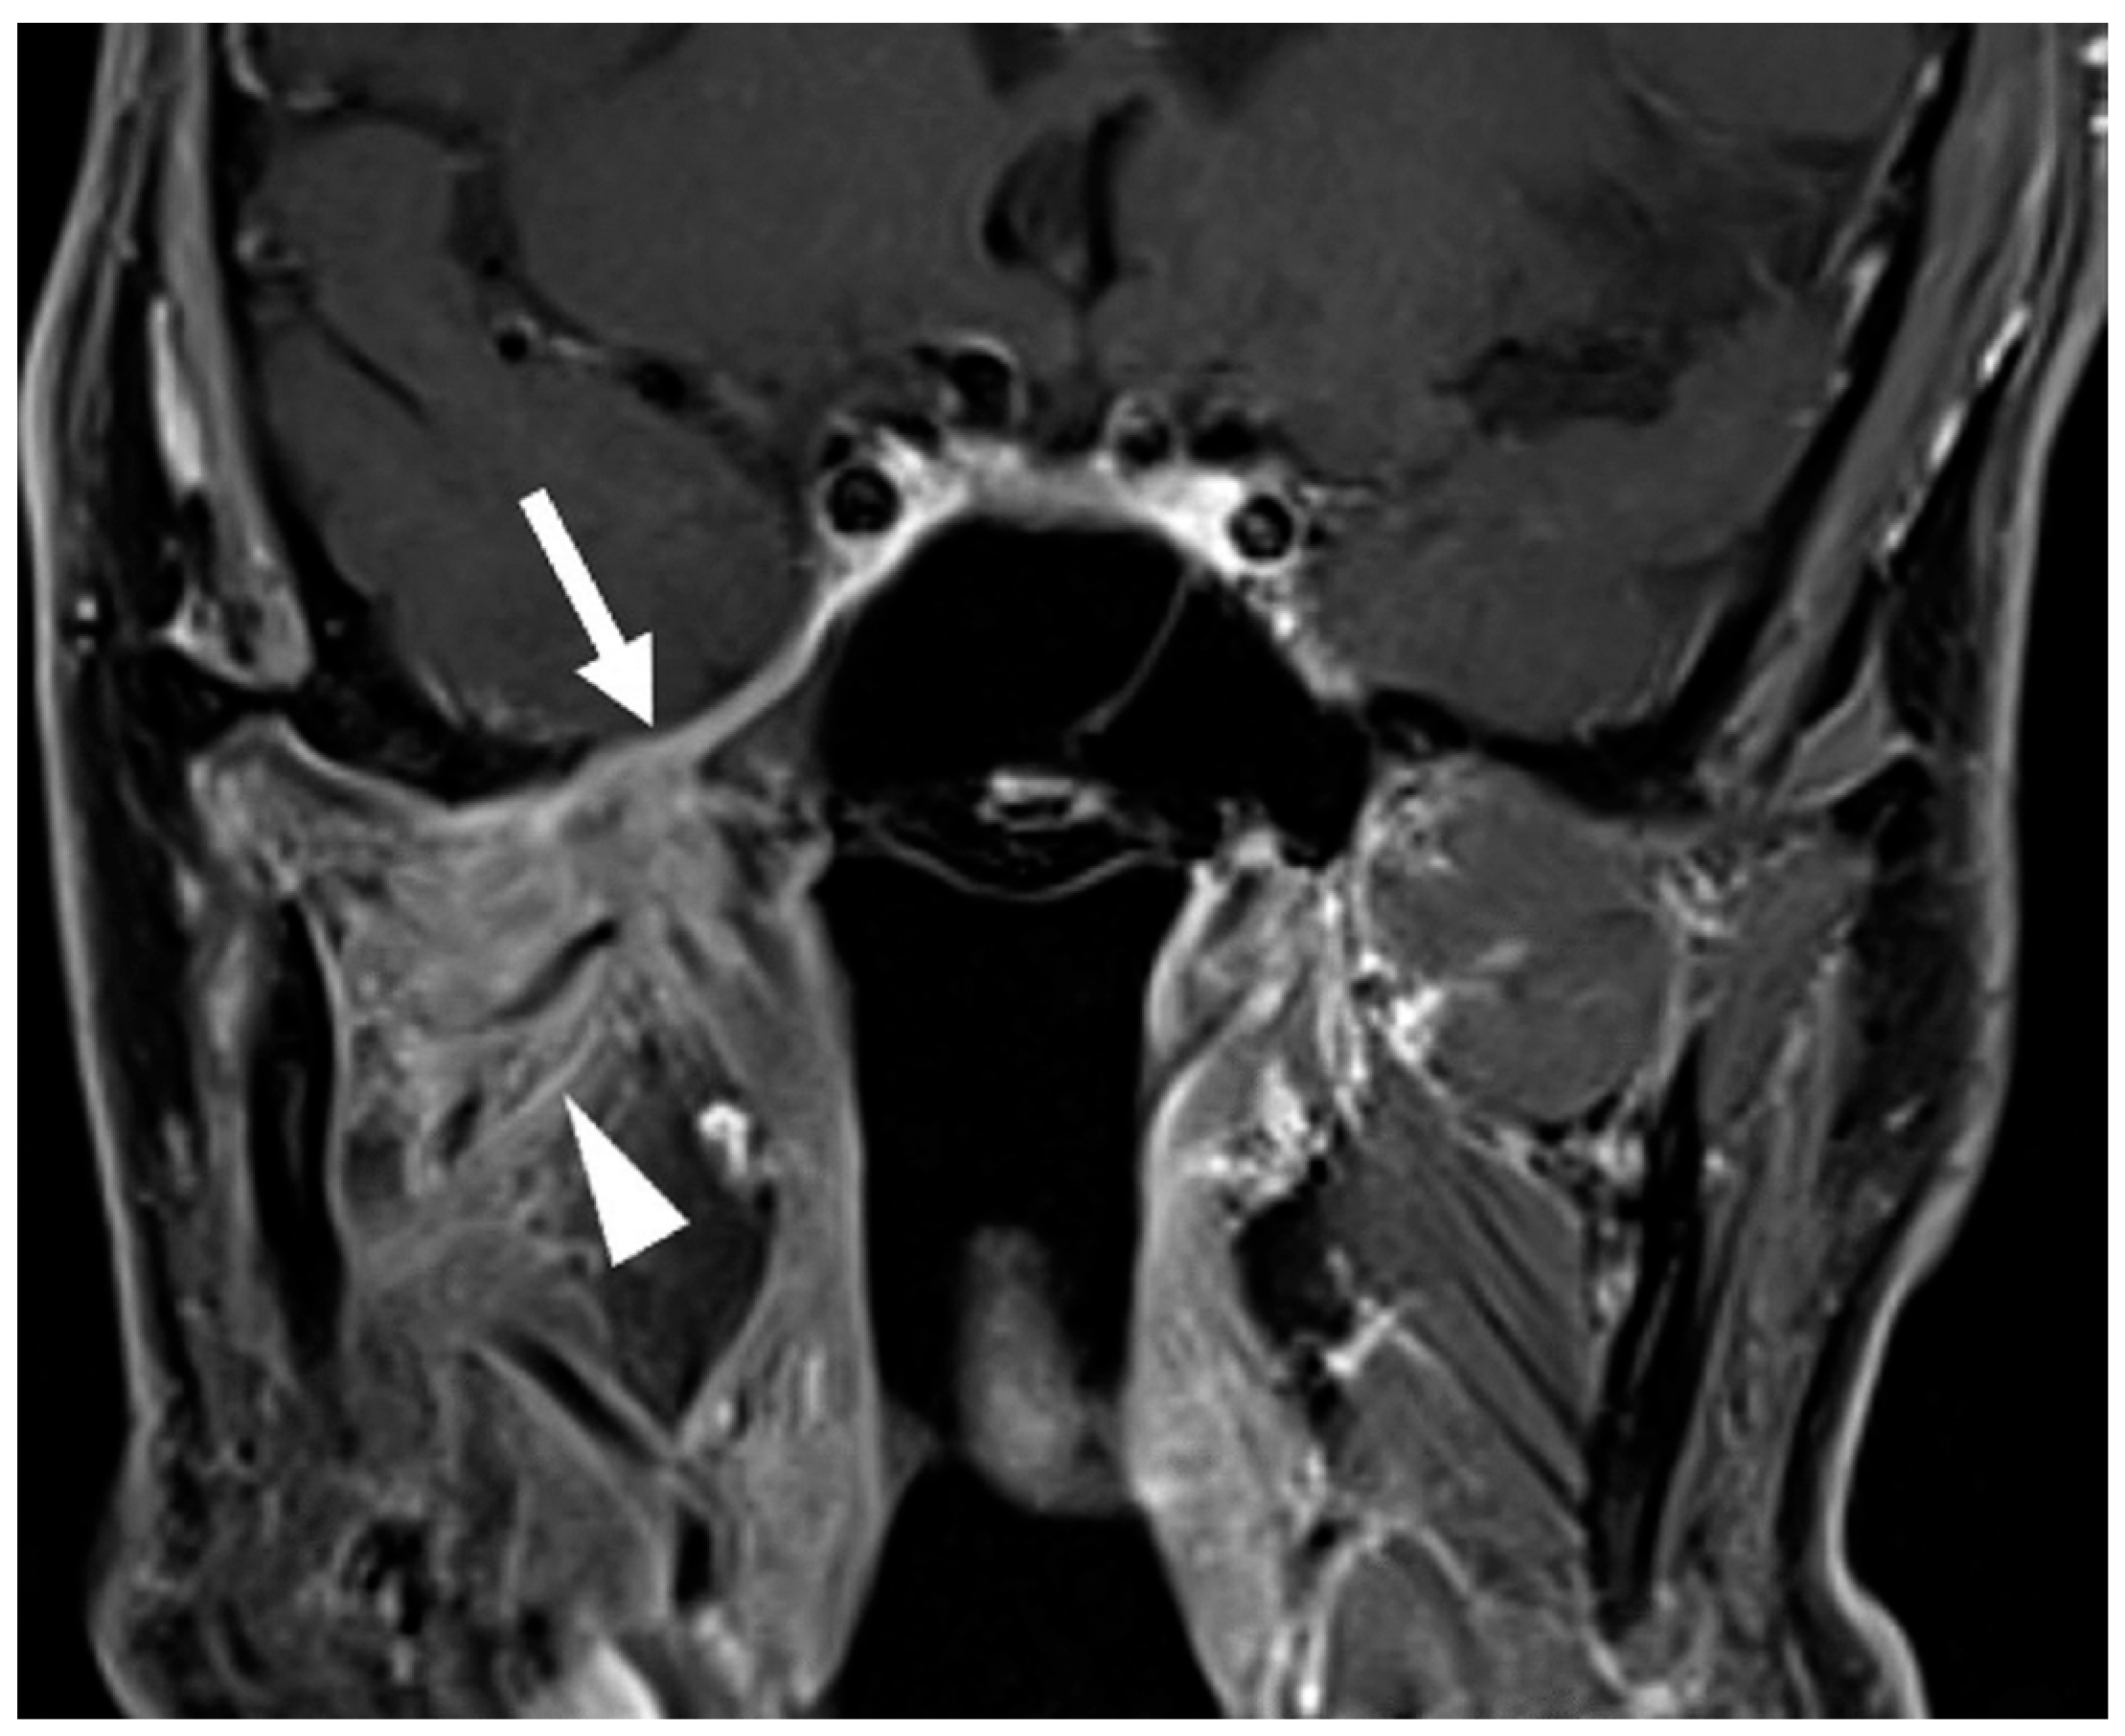

Post-treatment imaging evaluation of perineural tumor spread presents unique challenges. Changes such as denervation and foraminal widening may persist despite an effective treatment response. Indicators of response include decreased nerve thickening or enhancement on MRI and CT (Figure 3) and reduced metabolic uptake on FDG-PET [18,45]. However, radiographic findings may not fully correlate with disease activity; thus, clinical symptoms such as worsening pain and numbness remain the most reliable indicators of recurrence or progression [47].

Figure 3.

Post-treatment Examination Following Neoadjuvant Immunotherapy and Definitive Radiotherapy. Coronal T1-weighted, fat-saturated postcontrast image demonstrates decreased thickening and enhancement of the mandibular division of the right trigeminal nerve through the foramen ovale and right cavernous sinus (arrow, compared to Figure 2B). Note persistent abnormal enhancement of the right muscles of mastication (arrowhead) consistent with denervation changes; atrophy of the muscles did not resolve post-treatment.